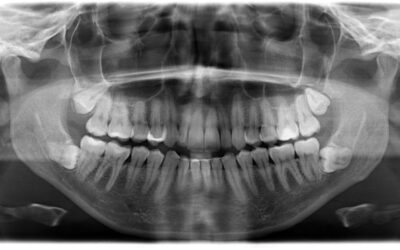

Dental X-rays: what they do (and why guessing is...